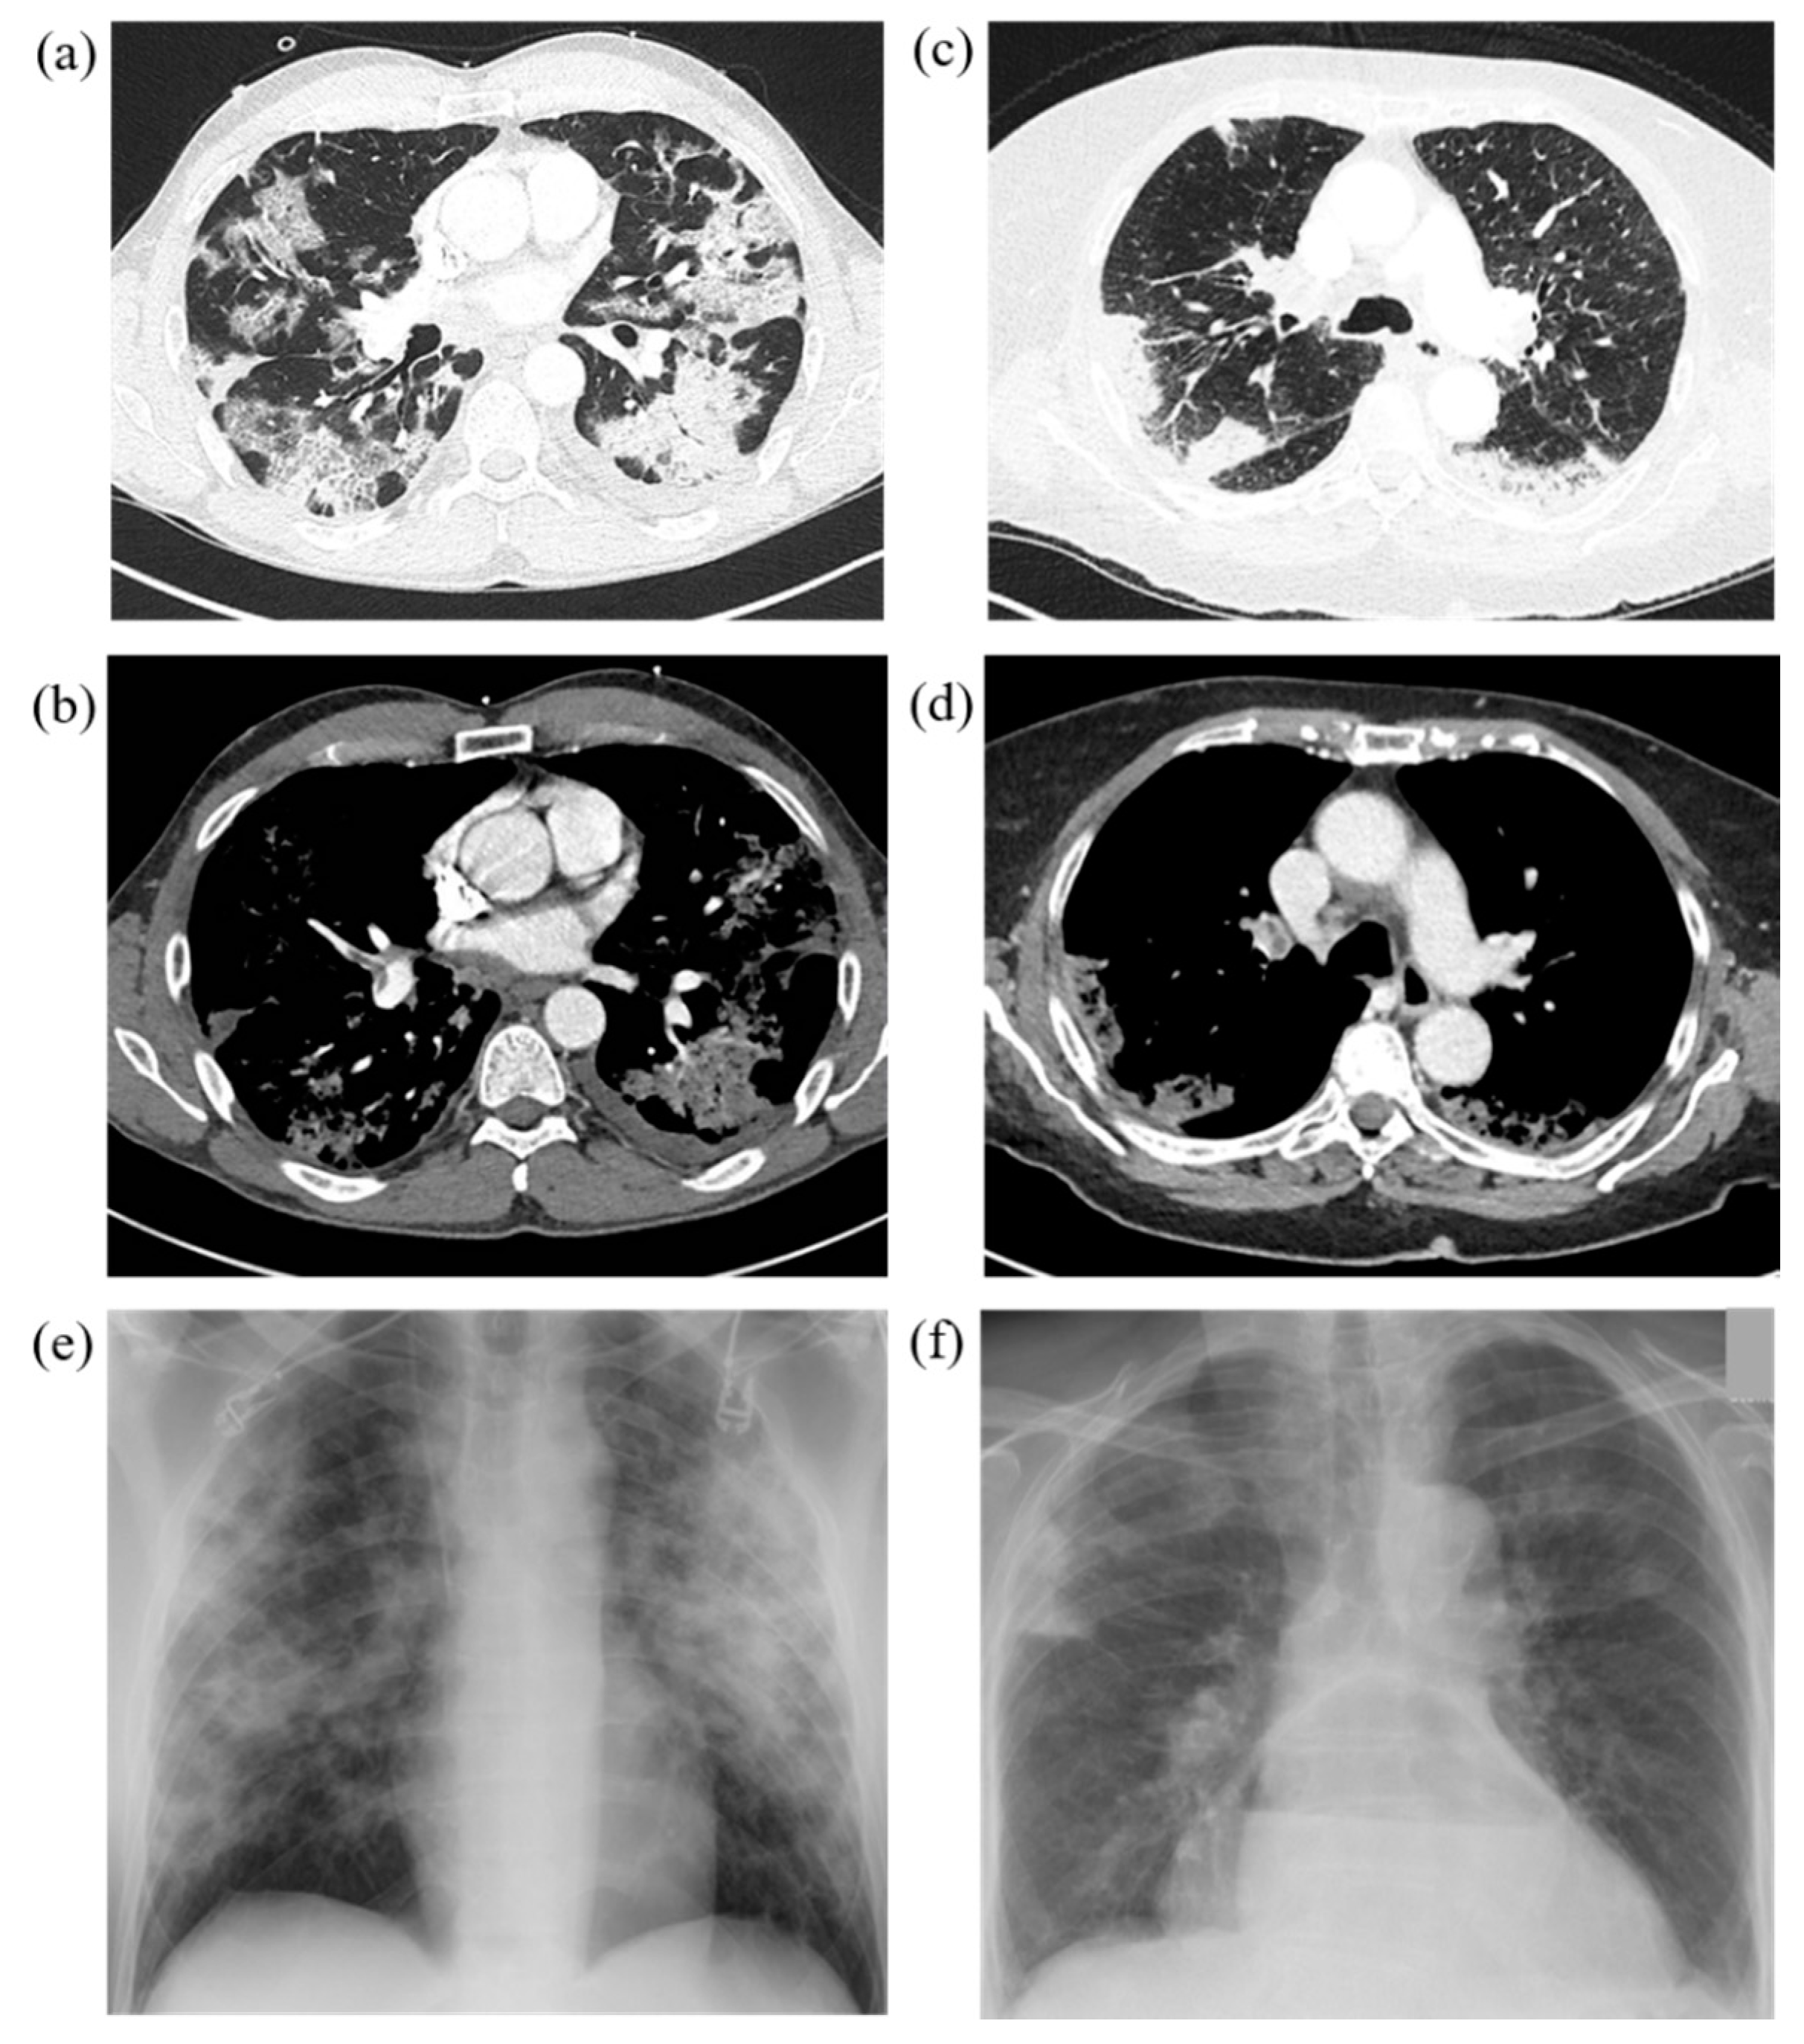

3.2. Imaging Findings within our Study Cohort

3.3. Group-related Differences in Imaging Characteristics

3.4. Group-Related Differences in Distribution Patterns